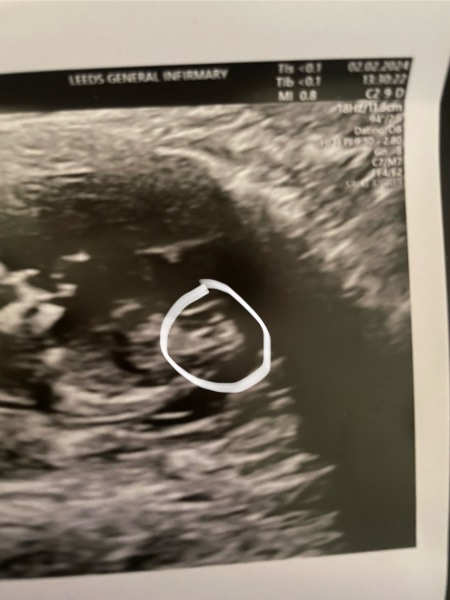

bethhmx · 03/02/2024 14:59

I had my 12 week scan yesterday.

The first picture is my scan, the second is a Google image… I’ve circled the ‘nub’ on my scan to help people see it clearly.

What are your thoughts? My thoughts are boy, but please share your opinions 😊